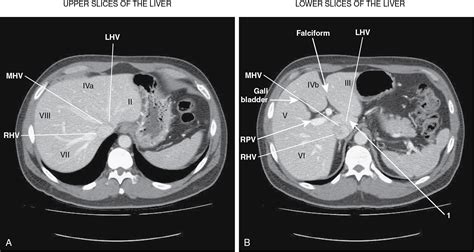

• Pre-surgical planning: Helping surgeons map out the liver's blood vessels and structural anatomy before procedures.

When a radiologist reviews the liver on CT, they look for specific "attentuation" patterns. Healthy liver tissue has a uniform appearance. Deviations from this indicate pathology. For example, fatty liver disease (steatosis) often presents as a darker, low-density appearance compared to the surrounding spleen or vessels. Conversely, iron overload (hemochromatosis) causes the liver to appear significantly brighter (more dense) on a scan.

Lesions detected during a scan are categorized by their density and how they "enhance" (light up) after the contrast dye is injected. A simple cyst, for instance, will remain dark and show no enhancement, while a hemangioma typically shows peripheral, nodular enhancement that slowly fills toward the center. Malignant tumors often exhibit "wash-out," where the contrast enters the lesion quickly but leaves it faster than the surrounding healthy liver tissue.